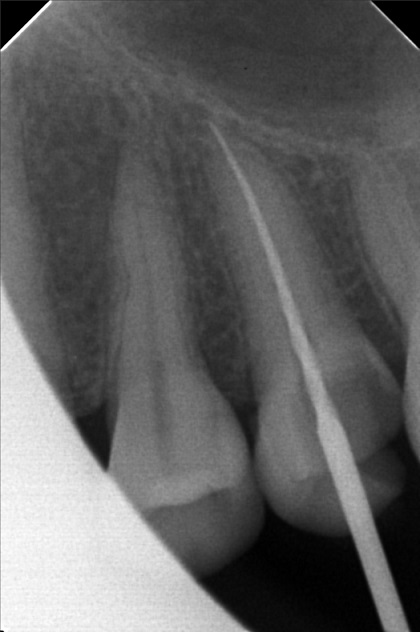

Edit Record Check our patient data records. Add patient information Patient Info Profile picture Last Name First Name Middle Name Birthdate Age Street Barangay City Country Zip Code Contact number Email Procedure 10/01/22 - OP(L); RESTO #26 ; #48; ACCESS #25 Scouting file #10 20mm; Closed with formocresol; Prescribed Tramadol +Paracetamol 325mg 10/08/22 - FILE 35 -19mm, CLOSED W/ CAMPHENOL; RESTO #22(LINGUAL), #47 (O & BUCCAL PIT) 10/15/22 - FILE 35 - 19mm, CLOSED W/ FORMECRESOL, RESTO #18(OB), #27, #28 10/22/22 - OBTURATE, FINAL RESTO#25, RESTO #16 (OL), #38 (O) File jamjam.jpg File 2 jamjam_02.jpg File 3 jamjam_03.jpg File 4 jamjam_04.jpg File 5 jamjam_05.jpg File 6 File 7 File 8 File 9 File 10 File 11 File 12 File 13 File 14 File 15 File 16 File 17 File 18 File 19 File 20 Retain Record Retain Record Yes No Save Your Changes